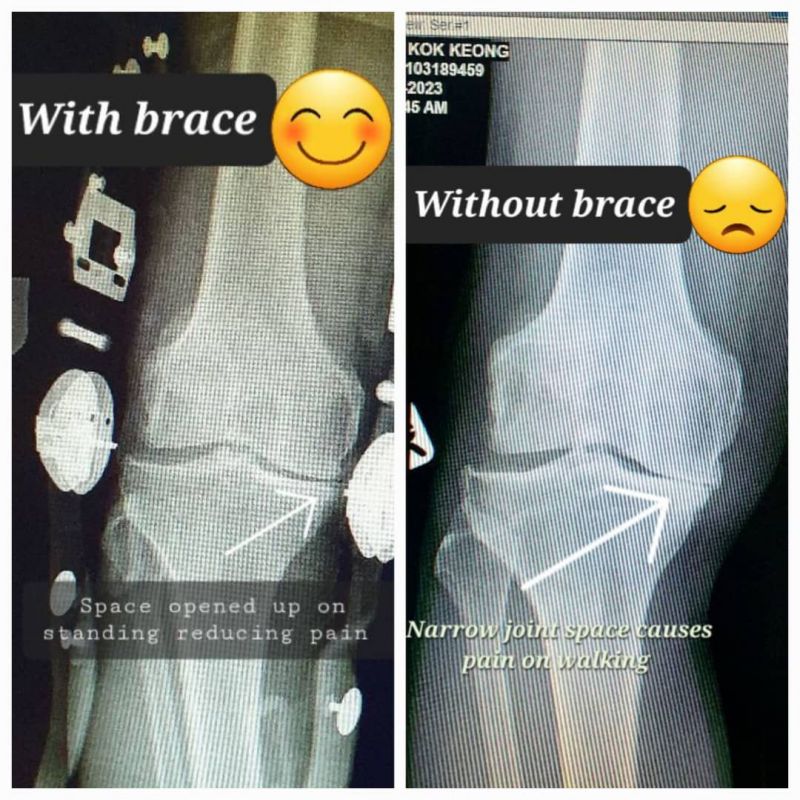

Indication: Right knee osteoarthritis

Device: Rebel Reliever